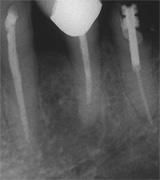

Der umfangreiche kariöse Defekt steuerte sehr bald hin auf die komplette Entfernung des Zahninnen­gewebes mit anschliessendem medikamentösen Wiederverschluss. Aufbissempfindlichkeit am Folgetermin ist immer Aufforderung zur erneuten Intensivsuche nach weiteren Kanälen, die hier einen 4. Ast zum Vorschein brachte. Nach 2 ausgelassenen Terminen

waren vorrangig Wiederherstellung von desinfizierender Einlage und provisorischer Füllung angezeigt. Eine weitere Woche später wurde in allen Kanälen das Medikament durch die endgültige Verschlussmasse ersetzt, worauf Zahn 36 mit 12-tägiger Verzögerung erneut zu rebellieren begann. Das hiess aus den hinteren Wurzeln Füllmaterial wieder raus und

Einlage erneut rein. Als es dann 4 Wochen später bei der hinteren Wur­zel aussen anzuschwellen begann und ein Medikamentenwechsel ohne Wir­kung blieb, wurden die hinteren Ka­näle abgefüllt und auch in gleicher Sitzung das überstopfte Material (Bild 1) mittels Resektion (Bild 2) von aussen entfernt.

Die ersten beiden Aufnahmen sind aus dem Jahr 1999, die 3. von 2006